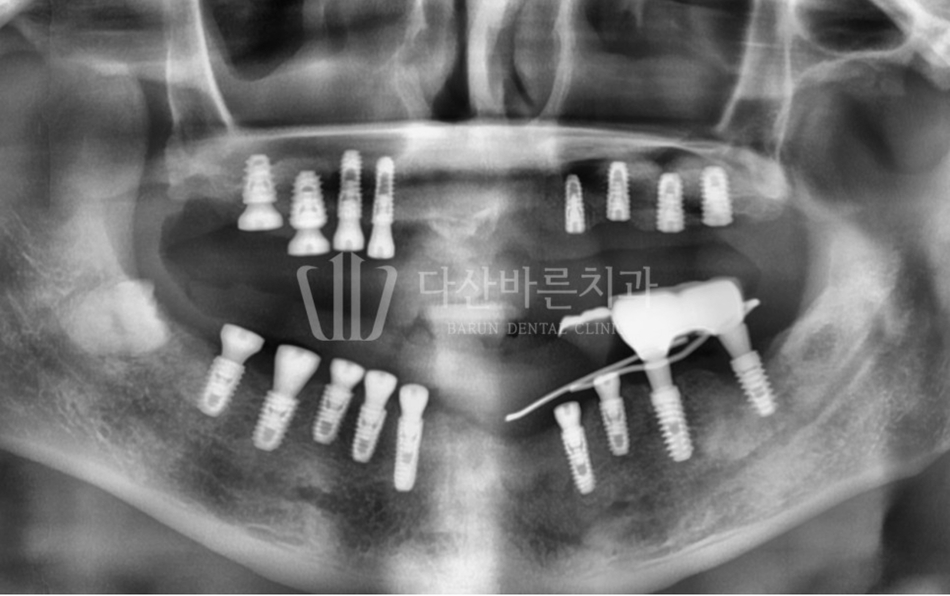

Ảnh dưới đây là ảnh chụp X-quang toàn cảnh quá trình đang điều trị.

Răng cửa hàm trên và hàm dưới đã phải tháo trụ implant do tiêu xương nướu nhiều do viêm quanh implant.

Ngoài ra, việc điều trị cấy ghép implant cũng được thực hiện ở các răng hàm

trên vốn chưa có răng và các răng hàm dưới sẽ rụng tự nhiên trong thời gian sắp tới.

Ngoài ra, một phẫu thuật thẩm mỹ implant đơn giản đã được thực hiện trên implant

hiện có ở phía răng hàm bên trái để ngăn ngừa mất thêm xương nướu.

(Hình bên dưới) Ở răng cửa trên và dưới nơi implant đã được tháo ra,

xương nướu được tái tạo thông qua ghép xương cùng lúc với việc implant được tháo ra.

Có vẻ như xương nướu vốn bị lõm xuống đã phục hồi trở lại hơi phẳng.

Tái tạo xương sau khi tháo implant

(Hình bên dưới) Ngoài ra, do răng bị mất đã lâu bị bỏ quên ở vùng răng hàm trên,

xương ổ răng còn lại không nhiều nên xương ổ răng được gia cố bằng phương pháp

‘nâng xoang hàm trên’ rồi tiến hành điều trị cấy ghép implant.